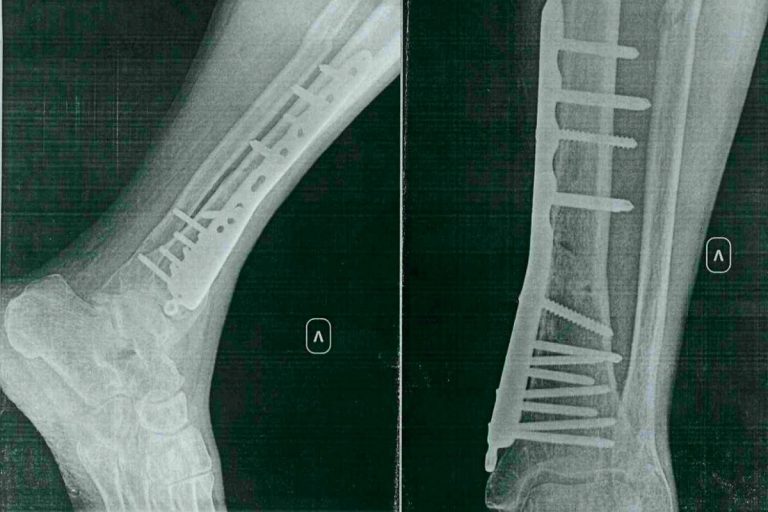

Как сообщил юрист, ведущий его дело, специалист получил открытый перелом нижней трети левой большеберцовой кости, средней трети левой малоберцовой кости, наружной лодыжки левой голени со смещением, поверхностный сухой некроз кожи нижней трети левой голени. Лечение и реабилитация продолжаются год и три месяца.